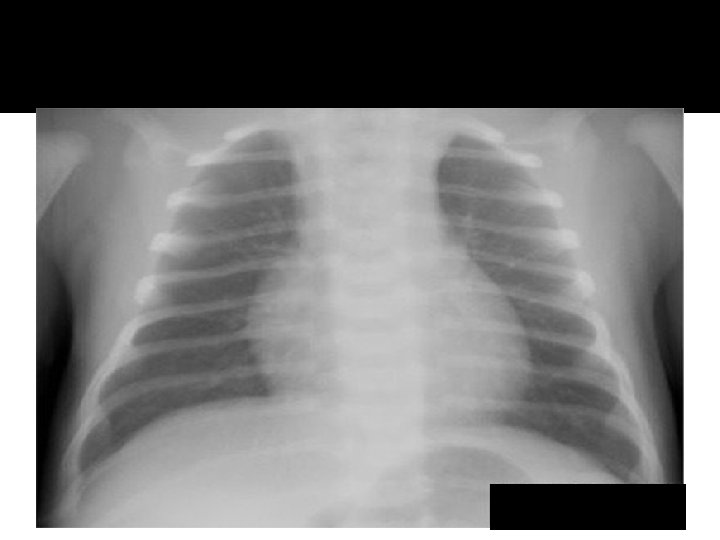

Atelectasis RML

Pneumonia lingula

Atelecasis RML